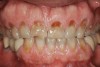

Figure 1   Classic presentation of the bruxism triad. Lateral wear pattern, generalized buccal tooth loss from erosion and abrasion, and history of sleep disruption.

Figure 1